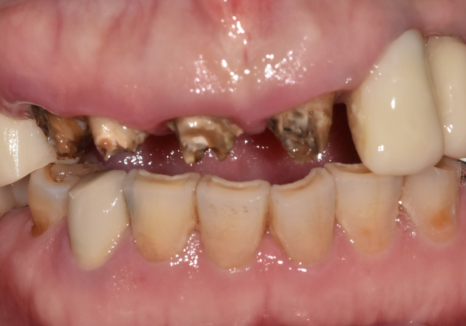

얼마 전, 3년 전에 하셨던

앞니 브릿지(#13~21)가 갑자기 빠져서

놀란 마음으로 내원하신 환자분이 계셨습니다.

평소 양치할 때 피가 나긴 했지만

통증이 없어 대수롭지 않게 생각하셨다고 해요.

빠진 브릿지를 제거하고 입안을

살펴보니 상황이 생각보다 좋지 않았는데요,

앞니 4개 모두 충치가 깊게 진행되어

검게 삭아버린 상태였고,